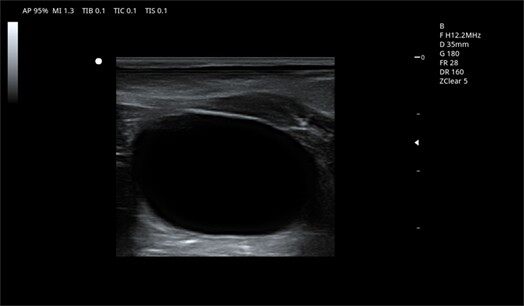

10L2PD ● 4.2-16.0MHz ● High-frequency linear array probe ● For Abdomen and Small Parts |

7L4PD ● 4.2-15.0MHz ● Linear array probe ● For Abdomen and Small Parts |